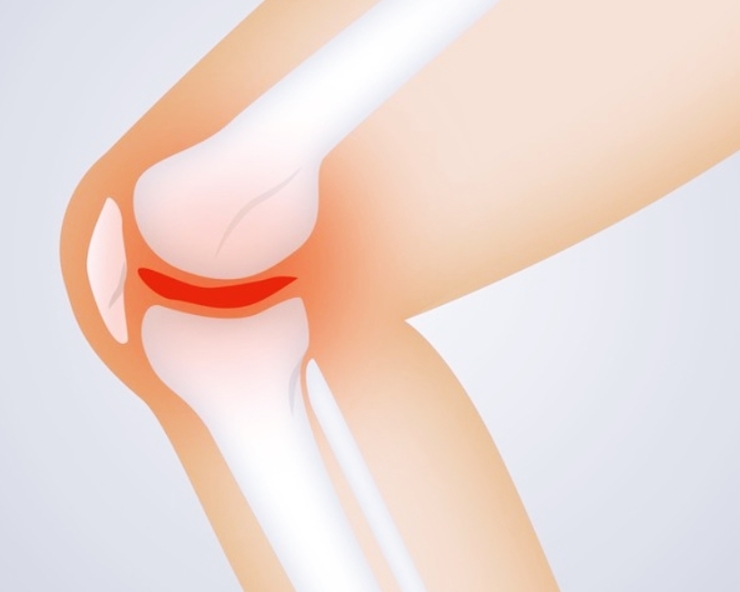

4. 관절에서 소리가 난다

관절을 움직일 때 '우두둑' 소리가 나거나 삐걱거리는 느낌이 들면 관절염 초기 증상일 수 있습니다. 건강한 관절은 부드럽게 움직이지만, 연골이 닳으면 뼈끼리 직접 맞닿아 소리가 나게 됩니다. 단순한 관절 소음과 달리, 통증과 함께 소리가 난다면 관절염 진행을 의심해봐야 합니다.